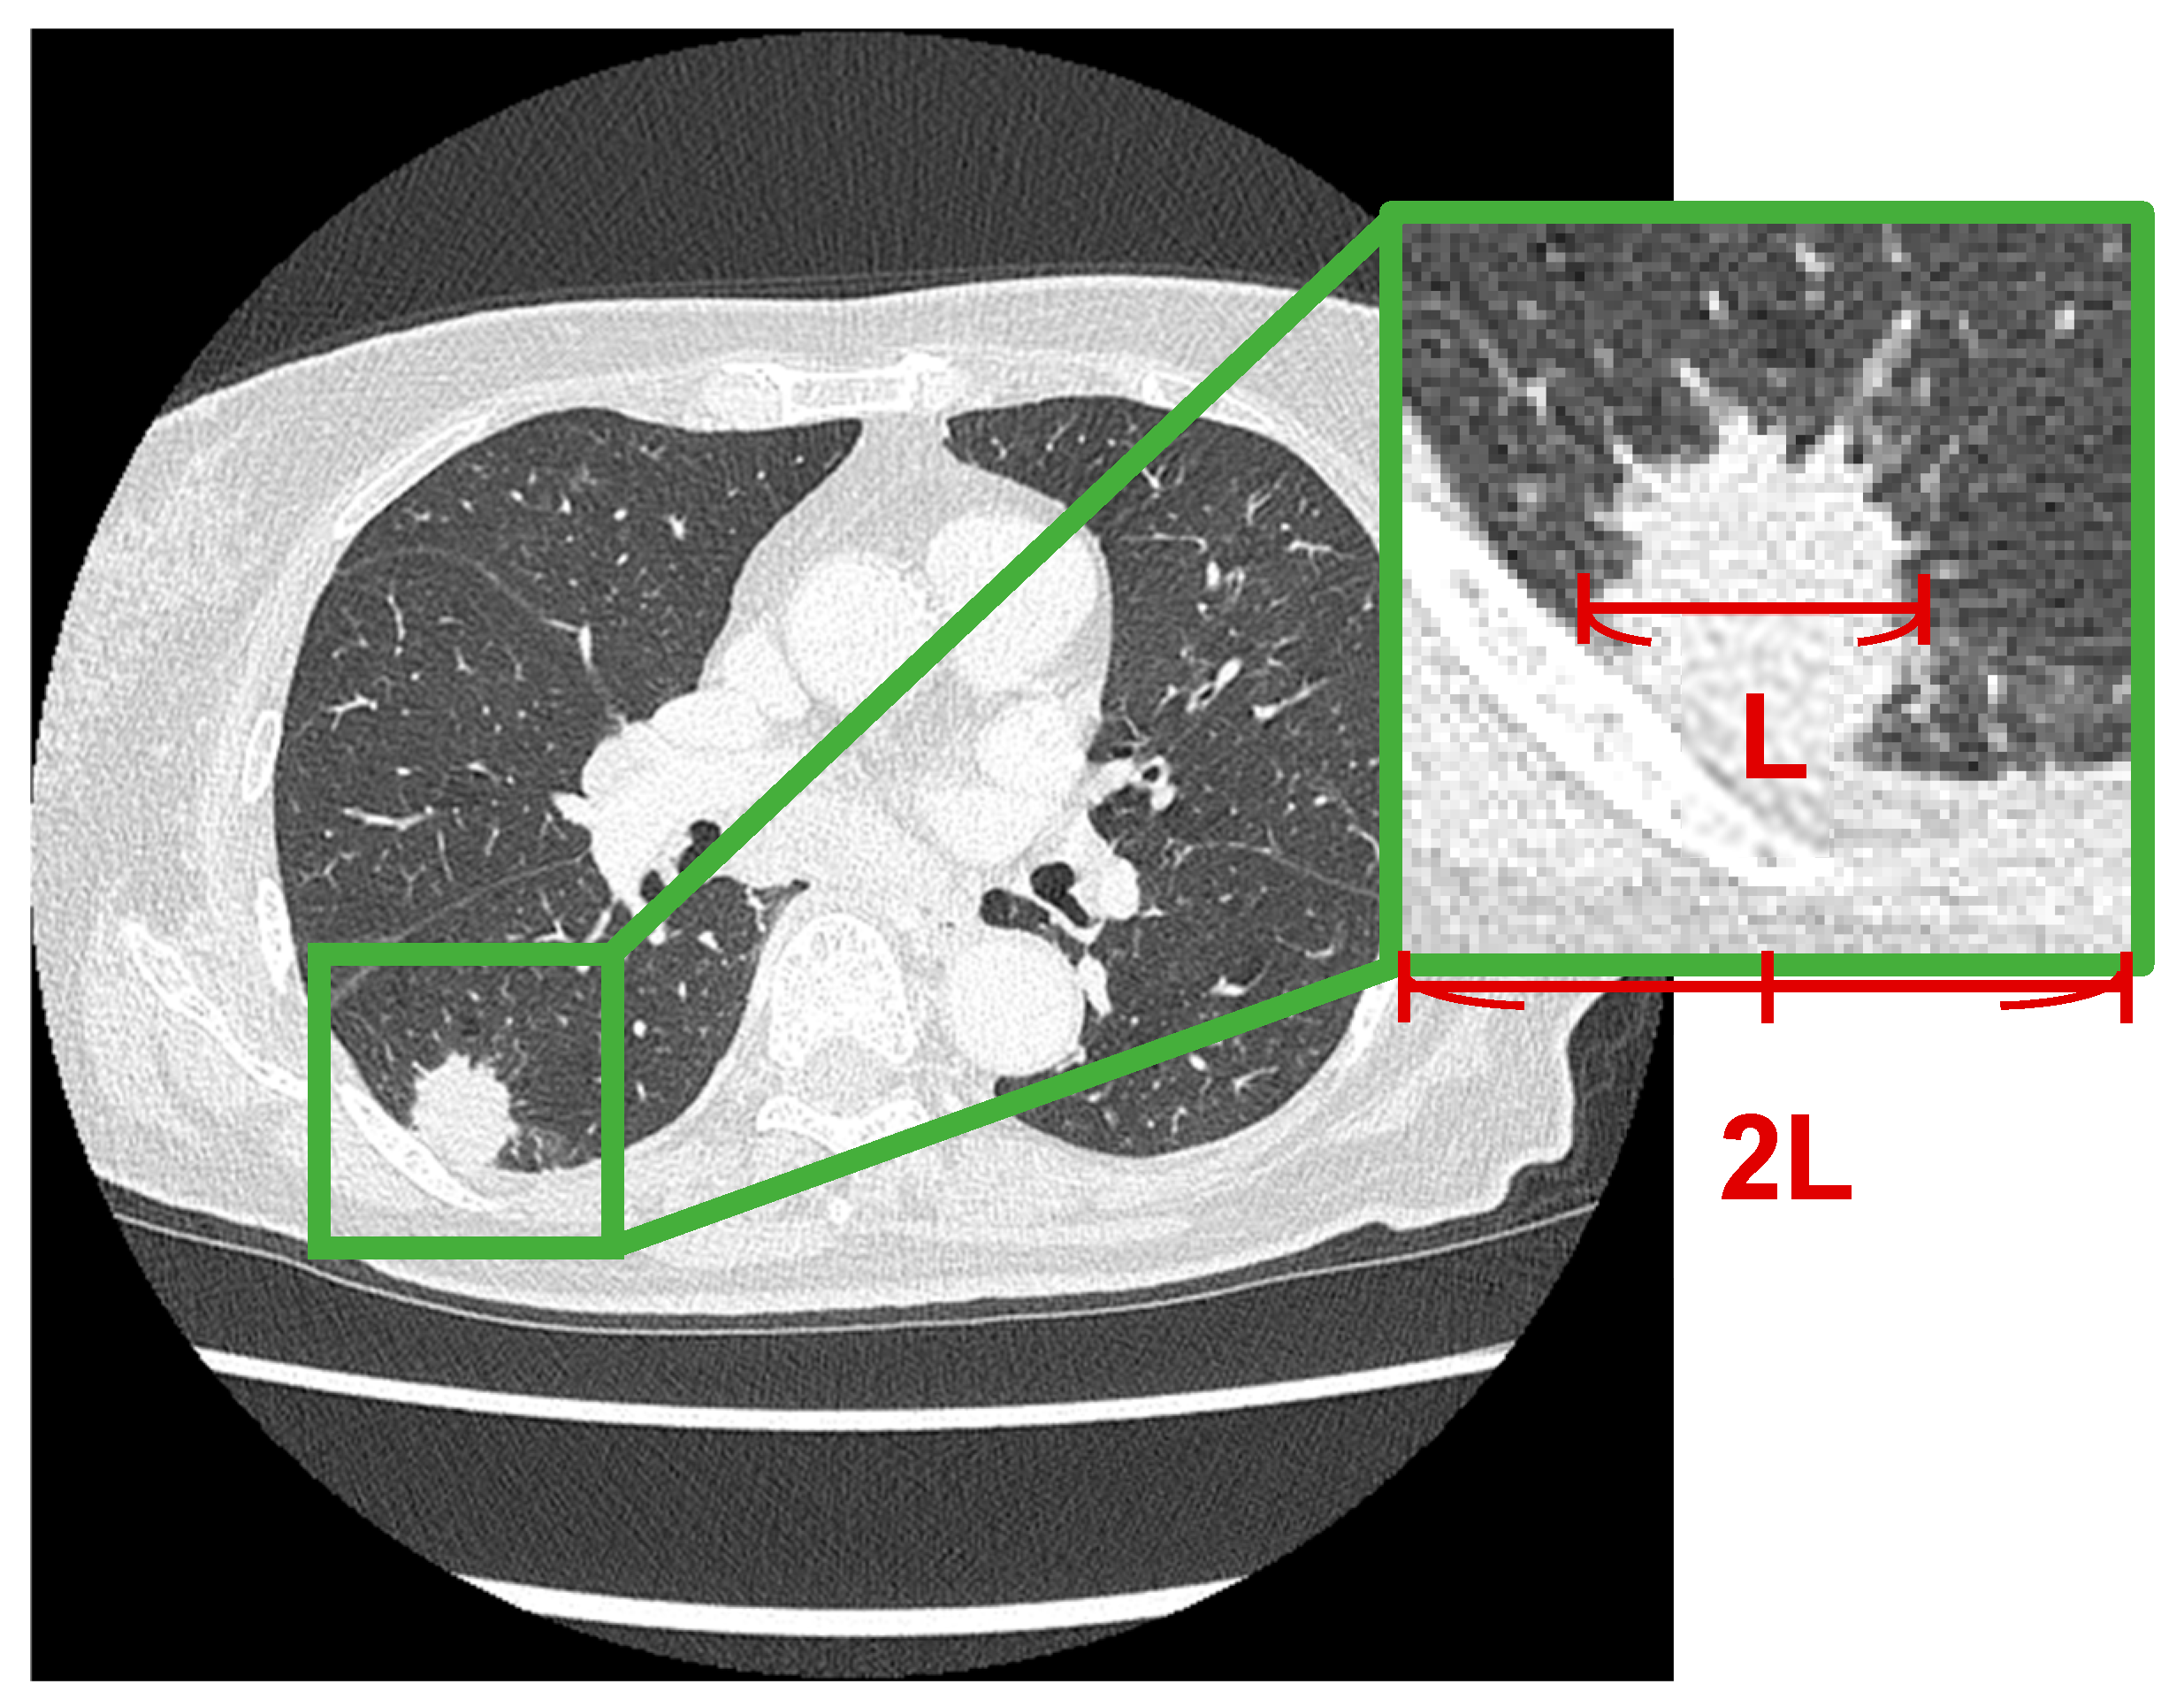

In this study, regions of interest (ROIs) around lung nodules were extracted from CT images as shown in Figure 2. In each case, an ROI centered on the tumor was extracted. The longest diameter of the lung nodule was measured, and a square ROI with a side length twice the measured diameter was defined based on the center of the nodule. This square region was cropped from the CT images.

Figure 2. Example of ROI extraction from CT images based on tumor long-axis diameter.